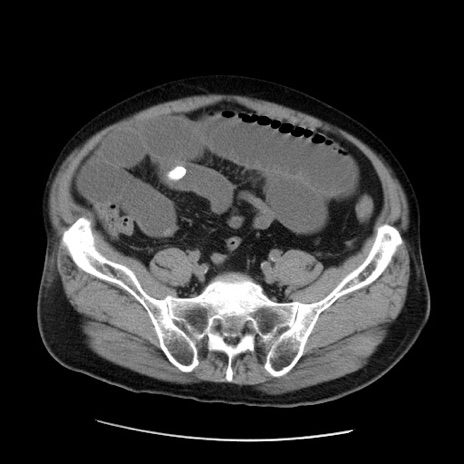

症例20(横断像)

【症例】 60歳代男性

【主訴】 腹部膨満、嘔吐

【現病歴】5日前頃より倦怠感を認め食事量減少し4日前の朝嘔吐、食事摂取困難となった。 3日前近医受診し点滴施行され整腸剤などを処方された。 当日他院を受診し、腹部膨満著明、炎症反応の上昇(CRP10.8、WBC11200)あり、紹介受診となる。

【身体所見】 意識JCS1 受け答えがはっきりしないBP 111/57mHg、 P 67bpm、、BT35.2°C、SpO2 97%(RA)、 腹部:膨隆、打診で鼓音あり、全体的に圧痛有り、腸蠕動音(-)、反跳痛ははっきりせず。

【データ】WBC 11400、CRP 14.20